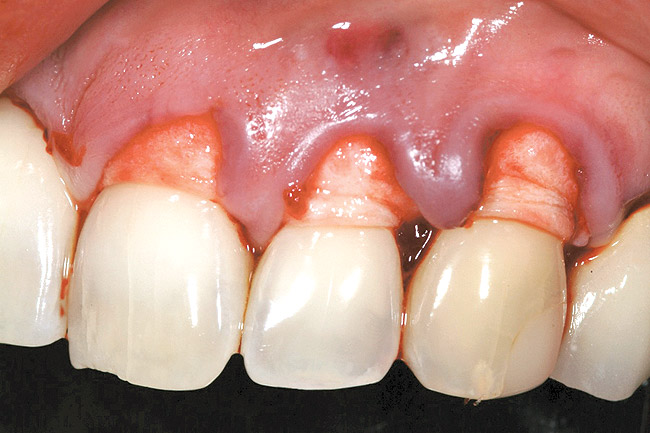

After administration of an appropriate local anesthetic, root preparation was accomplished by scaling and root planing with hand instrumentation and rotary instruments, followed by burnishing of the roots with 24% ethylene diaminetetra acetate (EDTA) and citric-acid solution (pH1) (Figure 5 and Figure 6).

Following the surgical technique previously referenced26 with some modifications, intrasulcular incisions were made around each tooth to be treated to a minimum of one tooth on each side of the affected teeth. The incision was not carried through the entire papillae apical to the contact point, roughly being contained between the mesial and distal line angle of each affected tooth. After the incisions were made, instruments to create a tunnel under each of the incised portions of the papillae were utilized to elevate the base of the papillae. The pouch was then created by blunt dissection using a mucoperiosteal elevator extending the reflection apically past the muco­gingival junction, and laterally to the facial aspect of the tunneled papillae. Occasionally, the papillae may separate in this process, as was the situation in this case. Deepening and mobilization of the pouch was then accomplished by sharp supraperiosteal dissection, which would allow for the pouch to be coronally advanced and cover the dermal tissue completely.

Figure 5  Case One Root preparation of teeth Nos. 9 through 11.

Figure 5

Figure 6  Case One Root preparation of teeth Nos. 9 and 10.

Figure 6